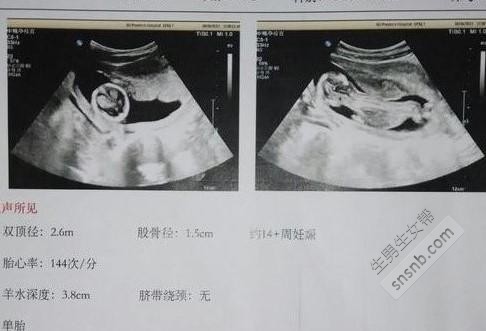

根据B超单子看男女。看孕囊:看怀孕40-50天时的B超单,观察孕囊的大小和形状就能看出胎儿的性别,孕囊形状是椭圆或圆形的是女宝宝,长条形的是男宝宝。看双顶径和股骨长:双顶径即胎儿的头部横直径,而股骨长则是胎儿的大腿骨长度,老一辈们的说法是,头大腿短的是男孩,即双顶径-股骨长>2,头和腿相差小的是女孩。